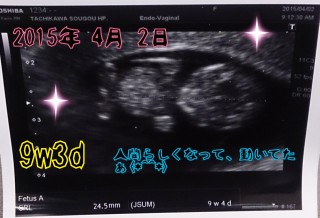

すっかり人間らしくなって、動いている様子もエコーで見ることができて嬉しかったです。赤ちゃんは、24.5ミリでした。

母子手帳をもらって初めての検診!三週間ぶりにエコーを見られるのが楽しみでした。つわりがひどくて辛いけど、成長してる証と思ってがんばります★